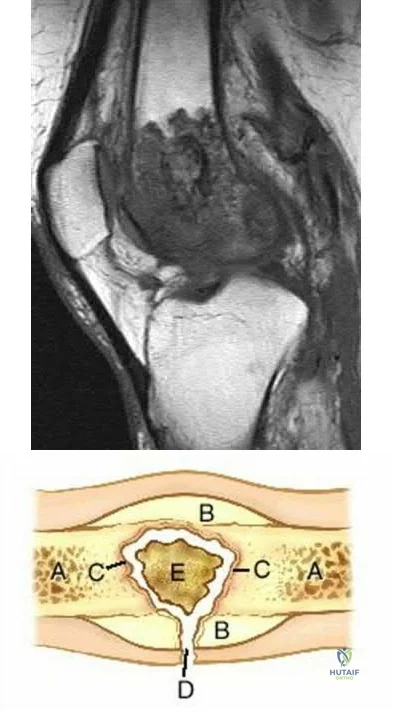

A 34-year-old man sustained a gunshot wound to the knee 18 months ago and was treated with bullet removal and a 10 day course of oral antibiotics. He now complains of 12 months duration of pain in the thigh and recent ulceration and drainage of the skin near the site of his gunshot wound. Physical exam is notable for a draining sinus tract, erythema and tenderness of the mid-thigh. He is afebrile. An MRI image of this patient is shown in Figure A. Which of the following is the most appropriate management?

In the referenced article by Parsons and Strauss, the management of chronic osteomyelitis is reviewed.